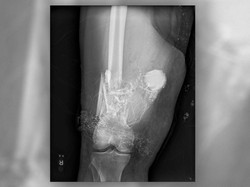

Sebuah proyektil peluru ditemukan di sebuah rumah konveksi di Tambaksari. Polisi masih menyelidiki adanya proyektil tersebut.